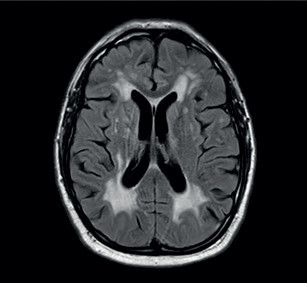

V lednu 2020 byl pacient opět hospitalizován na našem oddělení. V mezidobí mu byla přiznána invalidita I. stupně. Doporučenou ASA a atorvastatin přestal užívat. Byl skeptický a negativistický, měl potíže s krátkodobou pamětí, občas se objevil sklon k emoční labilitě a impulzivitě. Důvodem přijetí k hospitalizaci byla čtyři dny narůstající kmenová symptomatologie pod obrazem dysartrie, parézy n. III vlevo, parézy n. VII vlevo, lehké kvadruparézy a ataxie. Pacient byl orientovaný všemi modalitami, psychomotorické tempo bylo pomalejší. Řeč byla plynulá a srozumitelná. Stoj a chůze byly nestabilní, nebyl schopen samostatné chůze. Vyšetření MR mozku verifikovalo recentní ischemii v pontu velikosti 6 mm, splývající změny bílé hmoty byly v mírné progresi ve srovnání s předchozími vyšetřeními (obr. 3, obr. 4). Podle MRA a neurosonologie byl nález na extra‑ i intrakraniálních tepnách bez významnější patologie. Při biochemickém vyšetření séra byla nově zjištěna hyperhomocysteinemie. Hereditární trombofilie a Fabryho nemoc nebyly prokázány. Do medikace byla vrácena ASA, zvýšena dávka atorvastatinu (80 mg denně) a přidána kyselina listová. Kontrolní náběry na vaskulitidy byly negativní nebo v normě. Při kontrolním vyšetření likvoru byla zjištěna elevace bílkoviny (0,86 g/l), mírná lymfocytární pleocytóza, nespecifické zvýšení koncentrace cytokinů (IL‑1 a IL‑8), C‑reaktivního proteinu (CRP), C3 složky komplementu a vyšší koncentrace neurofilament i proteinu S100, ostatní nálezy byly obdobné jako v dubnu 2019. Při Mini mental testu (MMSE) dosáhl pacient 26 bodů, při Montrealském kognitivním testu (MoCA) činila dosažená hodnota 18. Narušena byla krátkodobá paměť, zrakově‑prostorové a exekutivní funkce. Neurologický deficit byl bez podstatné změny. Pro zvažovanou možnost malotepenné varianty primární angiitidy centrálního nervové systému (PACNS) byl intravenózně podán pulz methylprednisolonu v celkové dávce 3,5 g s následným tapperem per os, ale léčba nepřinesla žádoucí efekt. Pro depresivní ladění pacienta byl k léčbě přidán citalopram v dávce 20 mg denně a na noc mirtazapin v dávce 15 mg. Monitorace EKG a Holterovo monitorování EKG neprokázaly fibrilaci síní nebo jinou srdeční arytmii. Krevní tlak pacienta se pohyboval převážně v hodnotách do 120/80 mm Hg. Transtorakální a transezofageální echokardiografie, stejně jako ultrazvukové vyšetření ledvin a renálních tepen byly normální a odpovídaly věku. Pro upřesnění diagnózy, především směrem k malotepenné variantě PACNS a dědičným nemocem postihujícím bílou hmotu mozku včetně onemocnění CADASIL či CARASIL, byl pacient přeložen na neurologickou kliniku FN v Motole k doplnění digitální subtrakční angiografie (DSA) mozkových tepen, genetického vyšetření a případně i mozkové biopsie. Z provedených vyšetření: oční vyšetření nezjistilo vaskulitidu drobných cév oka, DSA neprokázala vaskulitidu mozkových tepen. Dle neuropsychologického vyšetření byl přítomen selektivní kognitivní deficit na úrovni syndromu mírné kognitivní poruchy (amnestické, vícedoménové a nehipokampální) s dominujícím zpomalením psychomotorického tempa, výrazným narušením pracovní paměti, výbavnosti a exekutivních či zrakově‑prostorových funkcí (především v oblasti konstrukce a ve zrakové diskriminaci komplexních podnětů). V prožívání dominovalo subdepresivní ladění, nestabilní emotivita a pohotovost k pláči. Při molekulárně genetickém vyšetření sekvenováním PCR produktů genu NOCTH3 byla prokázána patogenní heterozygotní mutace c.2989T>C(p.997R). Další léčba probíhala na neurologickém a rehabilitačním oddělení naší nemocnice. Poslední únorový den roku 2020 byl pacient propuštěn do domácí péče. Při propuštění byl schopen samostatné chůze s oporou francouzské hole nebo s rolátorem, modifikovaná Rankinova škála (mRS) = 3, skóre indexu Barthelové = 70, funkční míra nezávislosti (FIM) se pohybovala na hodnotě 5–7 ve většině činností (činnosti vykonával pacient buď sám, s pomůckami nebo pod dozorem druhé osoby). Plánované ambulantní kontroly byly znemožněny nástupem pandemie covidu‑19 a souvisejících epidemiologických opatření. V červnu 2021 absolvoval nemocný kontrolní vyšetření MR mozku se stacionárním nálezem rozsáhlé a splývající gliózy v obou mozkových hemisférách, mezencefalu a pontu. Stejně jako při předchozích vyšetřeních (únor 2019, leden 2020) nebyly postiženy temporální laloky, vnější kapsula byla postižena mírněji než kapsula vnitřní (obr. 5). Pacienta v říjnu 2021 a dubnu 2023 postihly další iCMP z levého karotického povodí, obě iCMP byly úspěšně léčeny intravenózní trombolýzou. V roce 2022 prodělal fokální levostranný motorický epileptický záchvat, pro který byla zahájena léčba valproátem v dávce 2× 500 mg denně. Prohlubuje se kognitivní deficit.

U našeho pacienta za první příznaky považujeme poruchy nálady a přechodnou poruchu orientace, výbavnosti i soustředění, které se objevily asi rok před rozvojem prvního ložiskového neurologického deficitu. Vyšetření mozku pomocí CT a MR prokázalo rozsáhlé postižení bílé hmoty obou hemisfér i pontu. Nicméně jak první klinické příznaky, tak nálezy na CT a MR mozku nebyly patognomické pro některé z cerebrovaskulárních onemocnění včetně CADASIL. Proti zvažované sporadické subkortikální leukoencefalopatii (historicky vžita jako Binswangerova nemoc) hovořil nejen věk pacienta (58 let), ale především nepřítomnost arteriální hypertenze, diabetes mellitus či kouření. Na druhou stranu ji ani definitivně nevylučovaly. V dalším průběhu se u našeho pacienta rozvinuly přechodné fokální neurologické příznaky a neuropsychiatrické projevy. Stanovení etiologie a určení diagnózy zpočátku ztěžoval i přístup pacienta s neakceptováním hospitalizace či s odkládáním ambulantních vyšetření. Což mohlo souviset i s poruchami nálady, negativistickým postojem a občasným impulzivním chováním při nastupující kognitivní poruše. V rámci úvodní diferenciální diagnostiky jsme zvažovali i jiné alternativy než cévní. Vyšetřením mozkomíšního mozku jsme neprokázali sclerosis multiplex či neuroboreliózu. V kontextu anamnézy, průběhu onemocnění a pomocných laboratorních vyšetření jsme vyloučili i neuromyelitis optica, progresivní multifokální leukoencefalopatii, jiné příčiny demence či paraneoplastický syndrom. Krevní testy na vaskulitidy byly negativní a normální titr protilátek proti fosfolipidům nesvědčil pro antifosfolipidový syndrom. Nepřítomnost dalších klinických projevů, normální hodnoty reaktantů akutní fáze (CRP, sedimentace) a normální nálezy dalších markerů autoimunitního onemocnění včetně revmatoidního faktoru, anti‑dsDNA, AMA, ANA, ANCA či ENA signalizovaly, že se nejedná o lupus či jinou systémovou vaskulitidu s postižením CNS. Postižení mozku (mozkový infarkt nebo akutní leukoencefalopatie) bývá většinou až pozdním projevem systémových vaskulitid.12 V tu dobu pacient neměl závažnější zdravotní potíže či je negoval a nebyl nakloněn dalšímu diagnostickému procesu nebo hospitalizaci. Brali jsme i v úvahu, že existují lidé s rozsáhlejšími změnami bílé hmoty, kteří nemají závažnější kognitivní úbytek nebo trpí jen mírně nespecifickými potížemi.13 Při recidivě fokální neurologické symptomatologie pod obrazem kmenových příznaků byla vyšetřením pomocí MR verifikována čerstvá ischemie v pontu v terénu rozsáhlých a splývavých změn bílé hmoty. Přítomna byla také kognitivní porucha. MR opět neprokázala postižení temporálních laloků ani výraznější postižení vnější kapsuly. Pro CADASIL bývají signifikantní právě změny ve vnější kapsule (až v 93 % případů) a v předních částech temporálních laloků (až u 86 % pacientů), a to již v počátečních stadiích.5,6 CTA či MRA mozkových tepen ani neurosonologické vyšetření neprokázaly signifikantní postižení extrakraniálních a intrakraniálních tepen. Při neurosonologickém vyšetření pacientů s onemocněním CADASIL mohou být patrné povšechně nízké toky, vyšší index rezistence a snížená vazomotorická rezerva.14 U našeho pacienta jsme tyto sonografické jevy nezaznamenali ani při opakovaném vyšetření. Diagnostický proces jsme směrovali i k dalším klinickým jednotkám. Zvažovali jsme malotepennou variantu PACNS. Tomu nahrávalo i opakované vyšetření mozkomíšního moku s nálezem proteinorachie, mírné lymfocytární pleocytózy a reaktantů akutní fáze (zvýšené hodnoty interleukinů 1 a 8 [IL‑1, IL‑8], C3 složky komplementu a CRP). Výsledek vyšetření likvoru je abnormální až u 90 % pacientů s PACNS, typická je proteinorachie a lymfocytární pleocytóza, která může být i mírná.15 Také negativní nález CTA nebo MRA mozkových tepen PACNS nevylučuje. I kognitivní deficit bývá charakteristický pro mikroangiopatickou formu PACNS a vyskytuje se asi u 67 % pacientů.12 Jako léčbu volby k možnému navození remise jsme v této fázi iniciálně zvolili methylprednisolon, ale bez klinického efektu. Neuropsychologické vyšetření specifikovalo kognitivní poruchu jako mírnou a s dominujícím narušením funkcí fronto‑subkortikálních okruhů. Pro trvající diagnostické rozpaky byly doplněny DSA mozkových tepen a genetické vyšetření (před mozkovou biopsií). DSA neprokázala změny svědčící pro vaskulitidu. Molekulárně genetické vyšetření potvrdilo mutaci v genu NOTCH3 na 19. chromozomu – patognomickou pro CADASIL. Stanovení definitivní diagnózy přineslo až genetické vyšetření, které bylo indikováno na základě anamnézy, klinického obrazu a nálezu na MR.